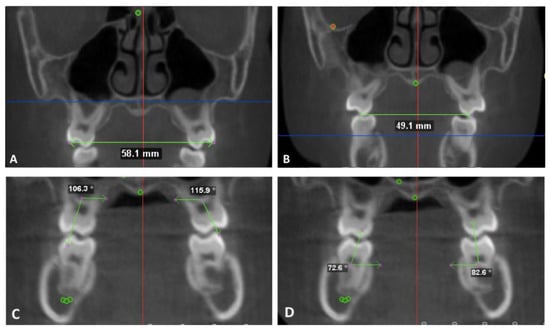

- Mx 1: 2 mm apical to the U6 CEJ on the T1 image. The most coronal axial cut on the T2 image.

- Mx 2: 6 mm apical to the U6 CEJ on the T1 image. The mid-axial cut between the most coronal and most apical cut on the T2 image

- Mx 3: 10 mm apical to the U6 CEJ on the T1 image. The most apical axial cut on the T2 image.

- Md 1: 2 mm apical to the L6 CEJ on the T1 image. The most coronal axial cut on the T2 image.

- Md 2: 6 mm apical to the L6 CEJ on the T1 image. The mid-axial cut between the most coronal and most apical cut on the T2 image

- Md 3: 10 mm apical to the L 6 CEJ on the T1 image. The most apical axial cut on the T2 image.

- Mandibular inferior border: the most inferior point on the mandibular border identified on a coronal section.